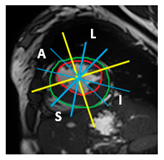

| Section | Segmented Cine-MRI | 17-Segment Model | Proposed 49-Sub-Segment Model | Number of Misclassifications |

| Apical section | ![]() | ![]() | ![]() | 3 sub-segments (1 sub-segment of segment 13 + 2 sub-segments of segment 15) |